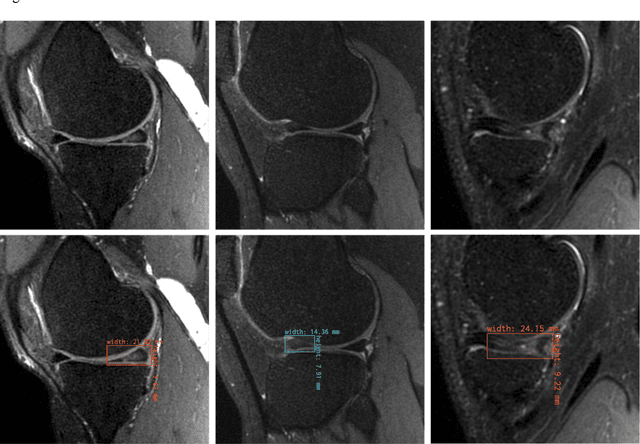

Abstract:This study investigates the relationship between deep learning (DL) image reconstruction quality and anomaly detection performance, and evaluates the efficacy of an artificial intelligence (AI) assistant in enhancing radiologists' interpretation of meniscal anomalies on reconstructed images. A retrospective study was conducted using an in-house reconstruction and anomaly detection pipeline to assess knee MR images from 896 patients. The original and 14 sets of DL-reconstructed images were evaluated using standard reconstruction and object detection metrics, alongside newly developed box-based reconstruction metrics. Two clinical radiologists reviewed a subset of 50 patients' images, both original and AI-assisted reconstructed, with subsequent assessment of their accuracy and performance characteristics. Results indicated that the structural similarity index (SSIM) showed a weaker correlation with anomaly detection metrics (mAP, r=0.64, p=0.01; F1 score, r=0.38, p=0.18), while box-based SSIM had a stronger association with detection performance (mAP, r=0.81, p<0.01; F1 score, r=0.65, p=0.01). Minor SSIM fluctuations did not affect detection outcomes, but significant changes reduced performance. Radiologists' AI-assisted evaluations demonstrated improved accuracy (86.0% without assistance vs. 88.3% with assistance, p<0.05) and interrater agreement (Cohen's kappa, 0.39 without assistance vs. 0.57 with assistance). An additional review led to the incorporation of 17 more lesions into the dataset. The proposed anomaly detection method shows promise in evaluating reconstruction algorithms for automated tasks and aiding radiologists in interpreting DL-reconstructed MR images.